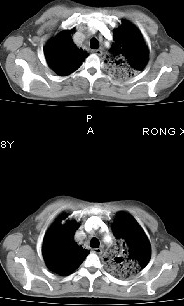

男68岁,反复发热、咳嗽,咯痰1月,曾有咯血史,双肺闻及呼吸音增粗。

左肺上叶尖后段及下叶多发实变阴影,内见支气管充气征,段以上支气管尚通畅,肺门区未见软组织肿块影,结合病人有反复发热病史,首先考虑感染性病变(干酪性肺炎不能排除),建议抗炎治疗后复查或结合纤支镜检查。

左肺上叶尖段及下叶干酪性肺炎可能性大,建议结合临床相关检查.右肺中叶炎症.建议治疗后复查.

该患者在25天前外圆平片见右肺中上肺野大片状影,(治疗不祥,在反复问病史后患者告诉;近一月住在新房内,搞装修),我认为首先考虑是感染,而且过敏性肺炎可能性大。

结果是过敏性肺炎,谢谢,楼主!